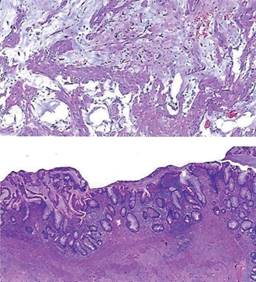

Reporte de patología 06/12/22: neoplasia mucinosa del apéndice cecal rota e inflamación aguda intensa pseudomixoma peritoneal secundario. El reporte recomienda estudio de inmunohistoquímica para confirmar diagnóstico y descartar malignidad (Figura 4).

Figura 4: Se observan cortes histológicos de tejido muscular liso con abundantes lagos de moco. Algunos fragmentos tisulares que, a nivel de mucosa, muestran criptas deformadas focalmente serradas, revestidas de epitelio cilíndrico simple de tipo enterocito que alternan con células caliciformes. La lámina propia exhibe infiltrado linfoide organizado.

Reporte de inmunohistoquímica 13/12/22: CKAE1/AE3 negativo, CK20 negativo, CK7 negativo, MUC5 negativo. Diagnóstico: tumor mucinoso con apendicitis aguda y adenomucinosis, probable cistoadenoma mucinoso.